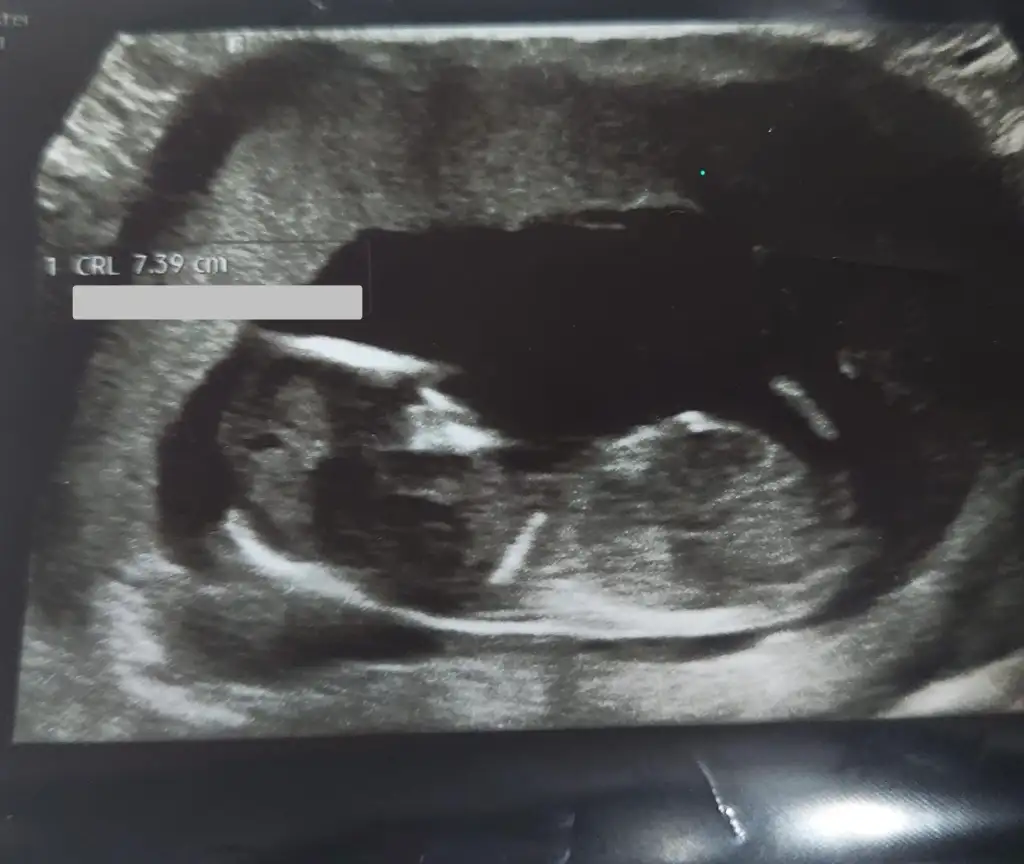

Merhaba yeni görüntüler var sizce ne olabilir doktorum bir tahminde bulundu ama sizin fikrinizi merak ediyorum

13+4 tahminde bulunabilir misiniz şimdiden teşekkür ederim.